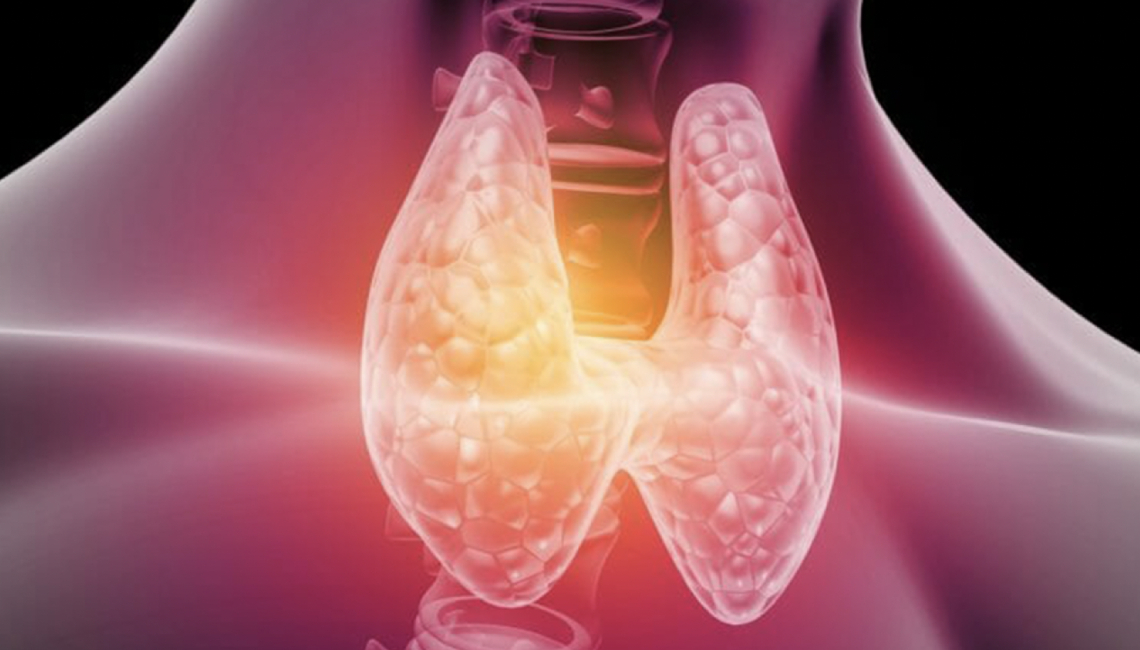

¿Qué es el Hipotiroidismo?

El hipotiroidismo es un trastorno en el que la glándula tiroides no produce suficiente hormona tiroidea. Esta hormona es esencial para regular los niveles de energía y metabolismo del cuerpo.